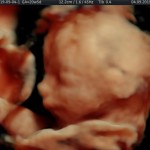

Modalidad de imagen ecográfica que permite evaluar, medir y capturar estructuras fetales superficiales e internas en 3 dimensiones (3D) y también en movimiento y en tiempo real (4D) con programas de realismo aumentado (HD LIVE) e imágenes tomografías fetales (TUI) mejorando significativamente la precisión en las mediciones fetales y la documentaciones de estructuras anatómicas.

Esta tecnología se puede utilizar desde la 6ta a la 40ma semana de embarazo.